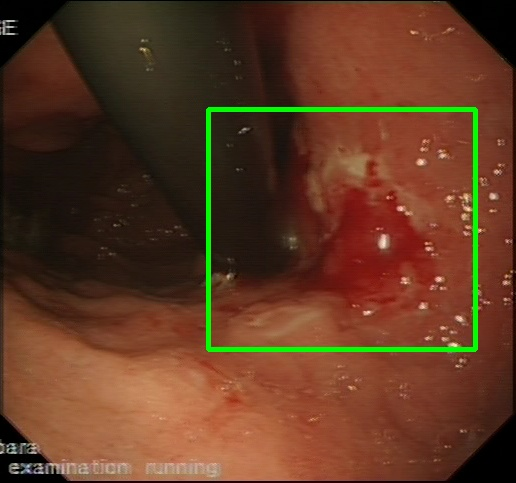

Gaussian Blur

Endoscopy GMAIMMbench Disease Diagnosis

Gaussian Blur - L0 (Original)

L0

L0 (Original)

Gaussian Blur - L1 (Moderate)

L1

L1 (Moderate)

Gaussian Blur - L2 (Severe)

L2

L2 (Severe)

Question

Focus on the square-highlighted area of this endoscopy image. What could be the potential diagnosis?

A barrett's esophagus B high-grade dysplasia C polyp D gastrointestinal tract cancer

Ground Truth: D. gastrointestinal tract cancer